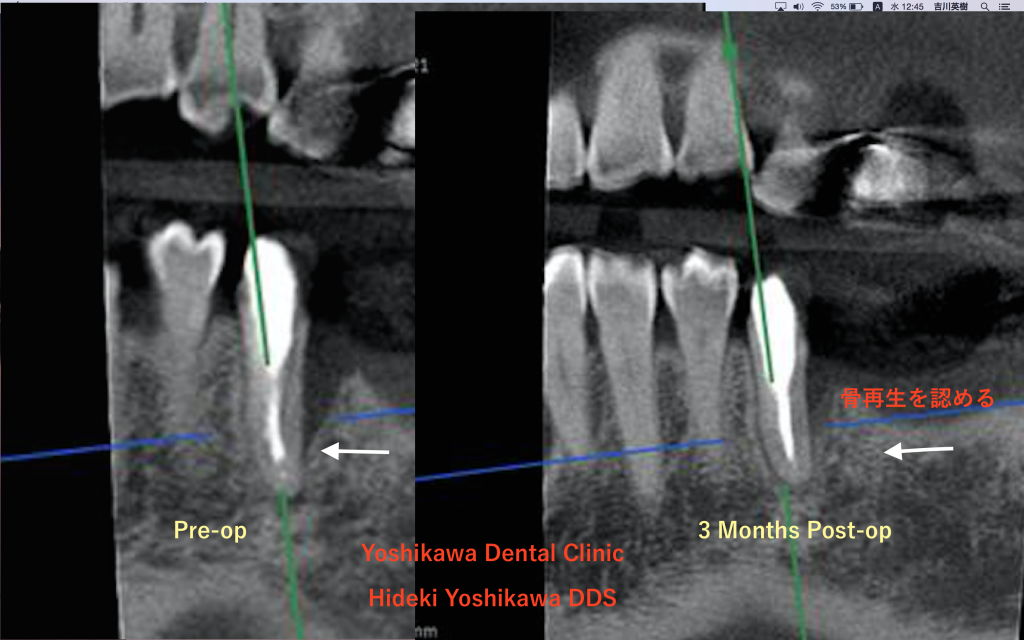

エムドゲインによる歯周組織再生療法 3ヶ月後

歯内・歯周病変をご存知ですか。

歯周病と歯内病変が合併した…